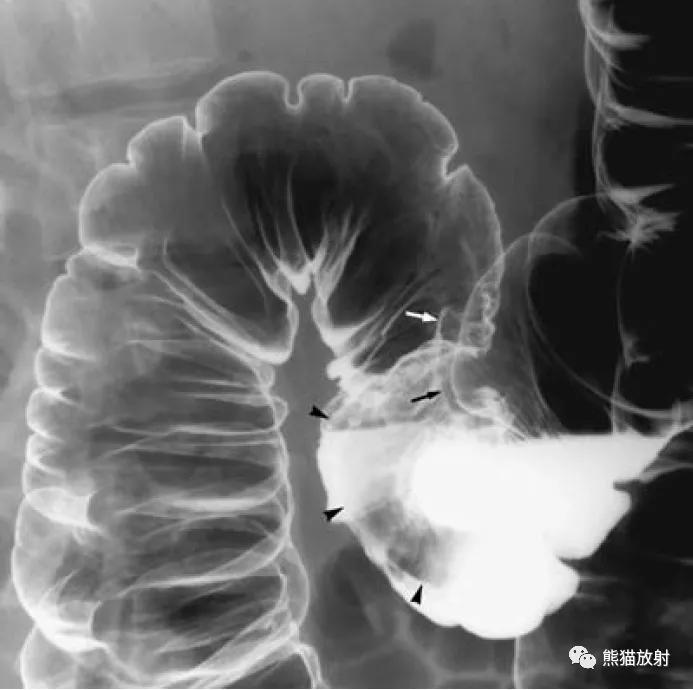

结肠腺癌。肠壁环形增厚,苹果核征;可见溃疡形成(箭)。

直肠远端癌(小箭),呈弥漫性地毯样浸润。息肉状浸润性直肠癌(大箭)。